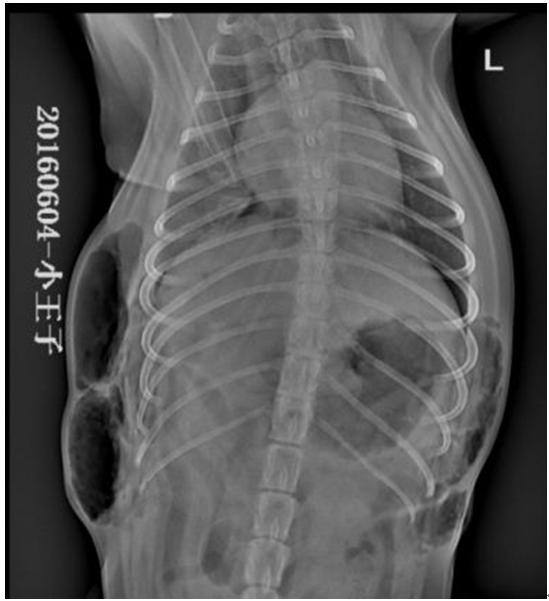

X线检查所示,右侧卧片可见,T9至L3之间背部皮下积气,肺脏萎缩,膈三角区密度降低,积气;仰卧位可见, T6至L3左侧胸部皮下气肿,右侧T8至L2右侧胸部皮下气肿,右侧膈角尖锐,密度降低,积气,提示胸壁透创并发气胸。

结合临床症状及X片检查结果,初诊为胸壁透创并发气胸。